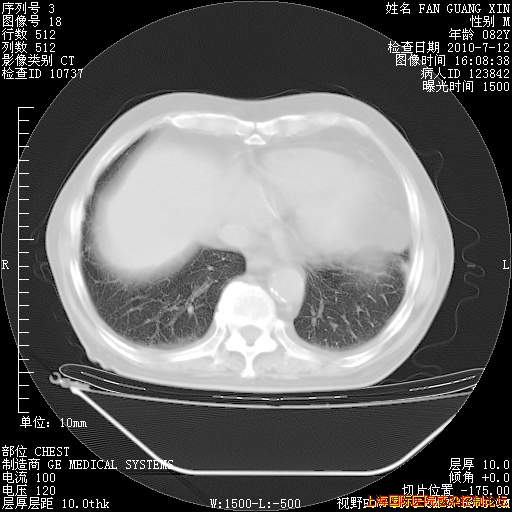

补发6月12日肺部CT肺窗

6月12日肺窗

整整相隔30天的肺部CT好像有所好转啊。甲强龙减量第3天,需要观察体温。